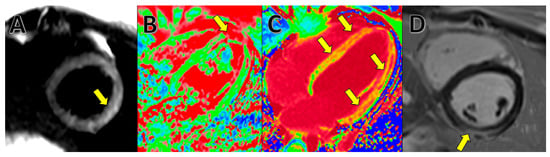

- Esposito, A.; Palmisano, A.; Natale, L.; Ligabue, G.; Peretto, G.; Lovato, L.; Vignale, D.; Fiocchi, F.; Marano, R.; Russo, V. Cardiac Magnetic Resonance Characterization of Myocarditis-Like Acute Cardiac Syndrome in COVID-19. JACC. Cardiovasc. Imaging 2020, 13, 2462. [Google Scholar] [CrossRef]

- D’Angelo, T.; Cattafi, A.; Carerj, M.L.; Booz, C.; Ascenti, G.; Cicero, G.; Blandino, A.; Mazziotti, S. Myocarditis After SARS-CoV-2 Vaccination: A Vaccine-Induced Reaction? Can. J. Cardiol. 2021, 37, 1665–1667. [Google Scholar] [CrossRef]

- Friedrich, M.G.; Marcotte, F. Cardiac magnetic resonance assessment of myocarditis. Circ. Cardiovasc. Imaging 2013, 6, 833–839. [Google Scholar] [CrossRef]

- Ferreira, V.M.; Schulz-Menger, J.; Holmvang, G.; Kramer, C.M.; Carbone, I.; Sechtem, U.; Kindermann, I.; Gutberlet, M.; Cooper, L.T.; Liu, P.; et al. Cardiovascular Magnetic Resonance in Nonischemic Myocardial Inflammation: Expert Recommendations. J. Am. Coll. Cardiol. 2018, 72, 3158–3176. [Google Scholar] [CrossRef] [PubMed]

- Kim, P.K.; Hong, Y.J.; Im, D.J.; Suh, Y.J.; Park, C.H.; Kim, J.Y.; Chang, S.; Lee, H.-J.; Hur, J.; Kim, Y.J.; et al. Myocardial T1 and T2 Mapping: Techniques and Clinical Applications. Korean J. Radiol. 2017, 18, 113. [Google Scholar] [CrossRef] [PubMed]

- Eitel, I.; Friedrich, M.G. T2-weighted cardiovascular magnetic resonance in acute cardiac disease. J. Cardiovasc. Magn. Reson. 2011, 13, 13. [Google Scholar] [CrossRef] [PubMed]

- O’Brien, A.T.; Gil, K.E.; Varghese, J.; Simonetti, O.P.; Zareba, K.M. T2 mapping in myocardial disease: A comprehensive review. J. Cardiovasc. Magn. Reson. 2022, 24, 33. [Google Scholar] [CrossRef] [PubMed]

4. Cardiac Magnetic Resonance (CMR)